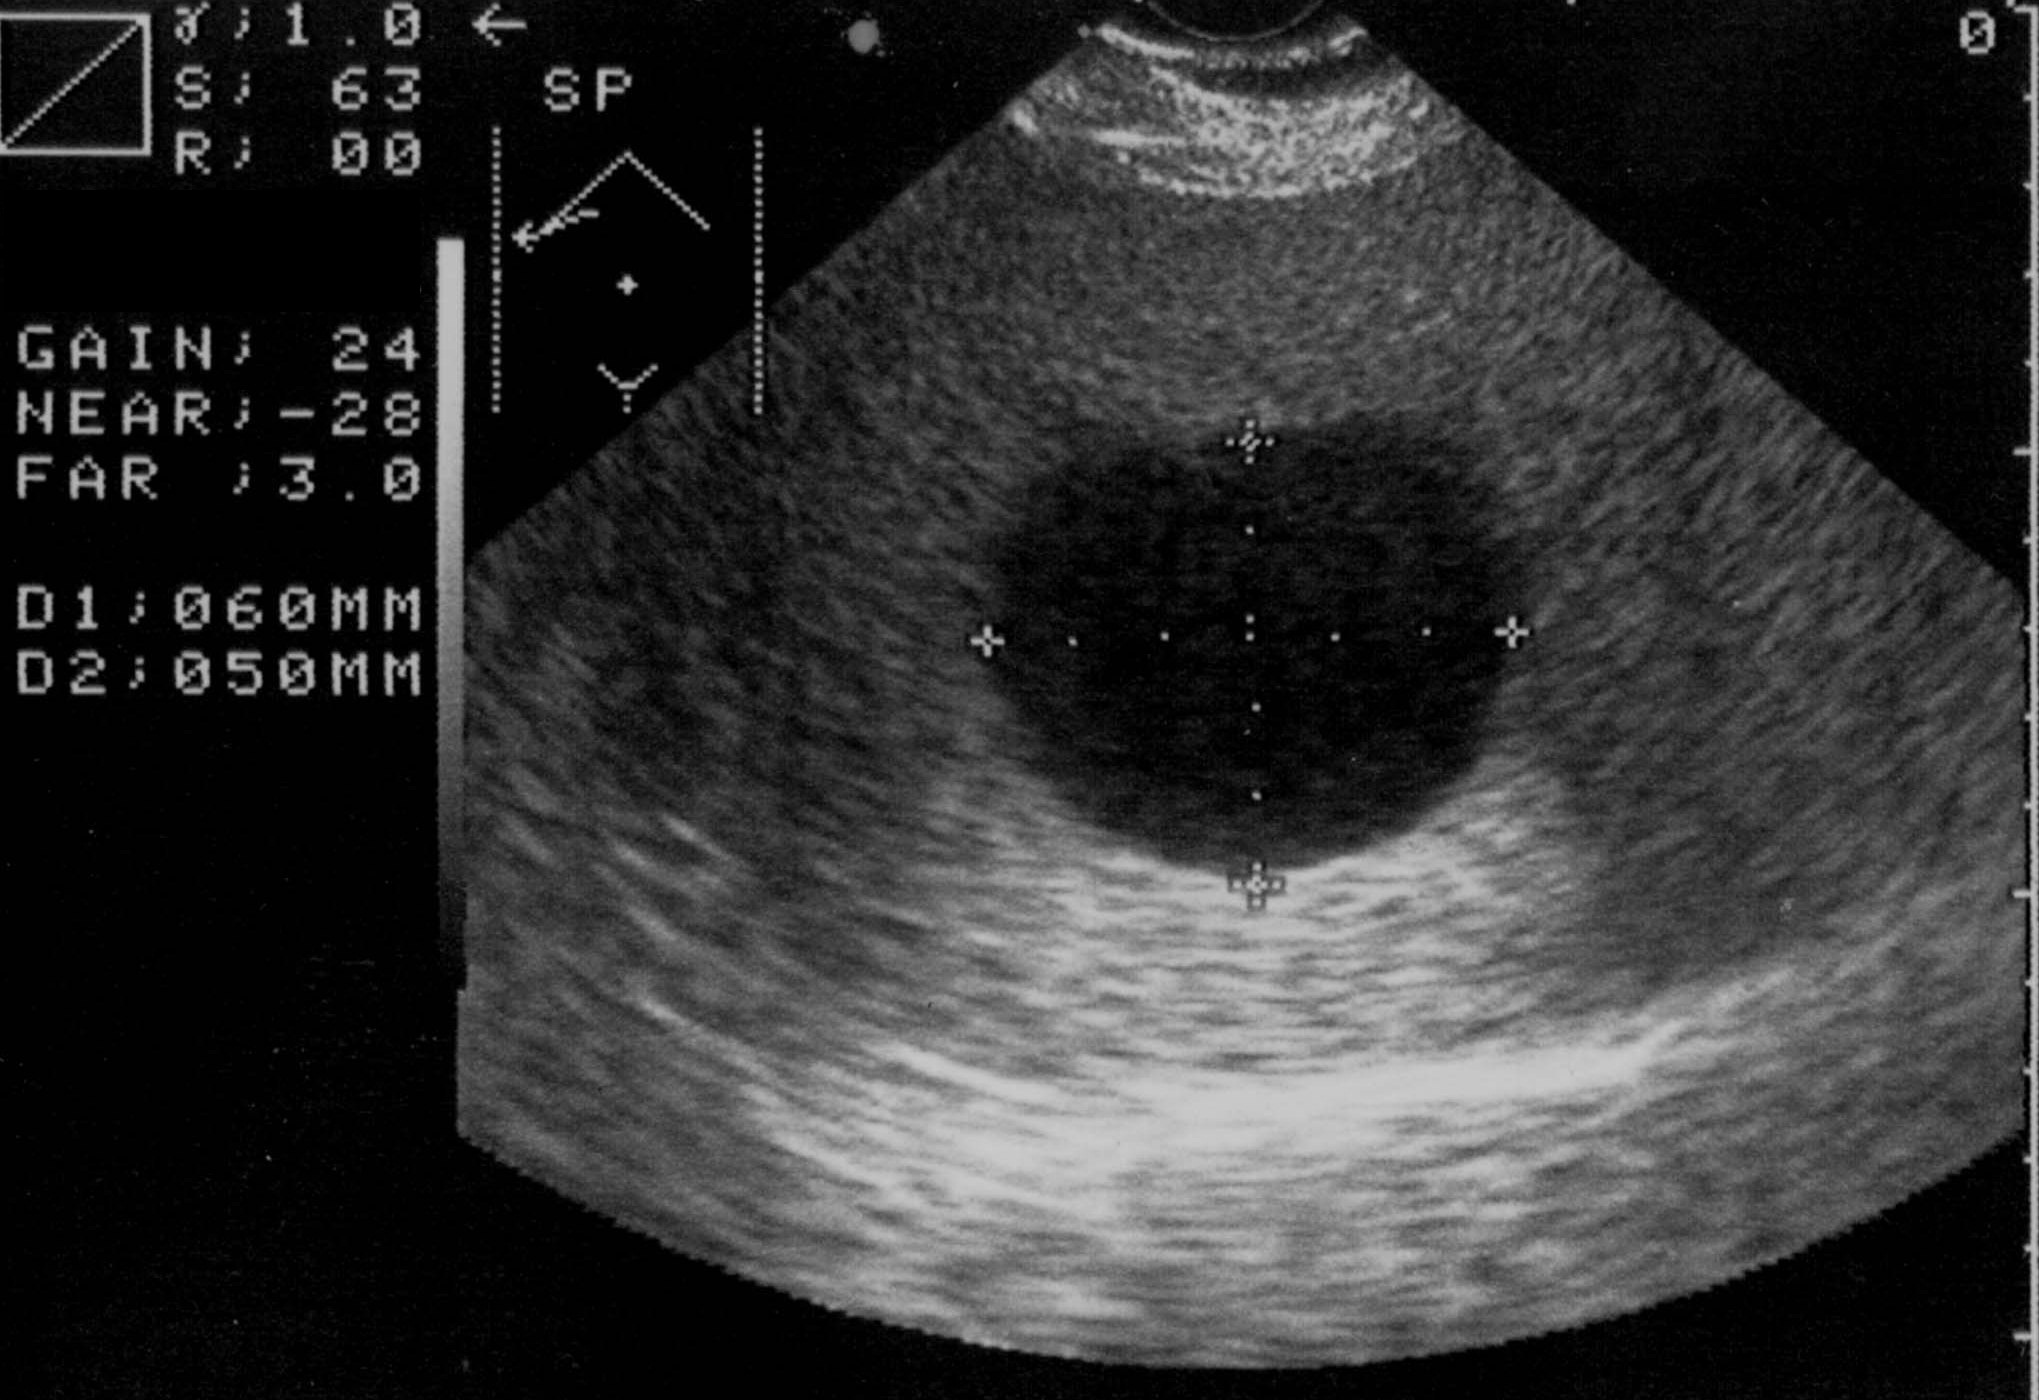

The simple cyst (Figure 16) indicates a difference from the multicystic liver only in the number of the cysts. Conversely, the polycystic liver (Figure 17) is an autosomal dominant inheritant disorder, in which the cystic conversion can be present in up to 70-80% of the liver parenchyma due to the large number of the cysts. It often accompanies with polycystic kidneys, whilst the entire polycystic syndrome – if also polycystic affection of the pancreas is also associated – occurs very rarely.

Figure 16: Simple liver cyst, US